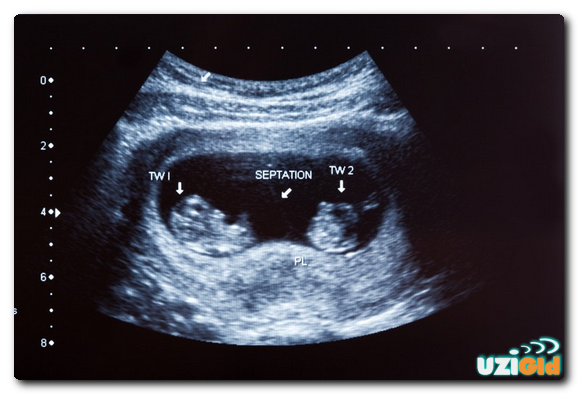

Самое раннее время, чтобы сказать, произошло ли зачатие, составляет пять недель. За это время врач имеет возможность увидеть эмбрионы в матке и определить их количество. На этом этапе начинает формироваться сердце ребенка, и с 8-й недели вы можете слышать биение двух и более сердец. Также это сигнал о многоплодной беременности.

На ранних стадиях шансы увидеть двойню или тройню намного выше, если дети состоят из нескольких яйцеклеток. Симптомы таковы, что у каждого эмбриона есть отдельная плацента и плодное яйцо, что хорошо видно на мониторе. Если у однояйцевых близнецов всегда общая плацента, амниотические пузыри могут быть разными или общими. В этом случае обычно невозможно увидеть более одного эмбриона до 10-12 недель.